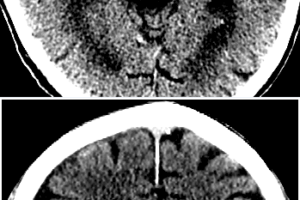

Early Signs of Stroke on CT

Despite its poor sensitivity for detecting embolic strokes, head CT scan remains the initial imaging modality in the work up of suspected acute stroke. The rationale is to initially rule out hemorrhagic...